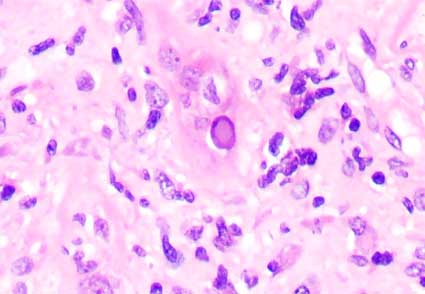

Figura 3.

H&E, X400.